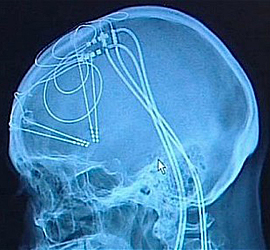

DBS, or Deep Brain Stimulation: we’ve heard of it, but what the hell is it? Can placing electrodes in your brain really fight the forces driving addiction? DBS is a surgical procedure performed under general anesthesia, after MRI scans have identified a target in the brain. A small area of the scalp is removed, and a probe places an electrode at the desired location. Mild electrical impulses then stimulate the area in question. A recent article in the journal Addiction calls for well-controlled clinical trials of DBS for addiction, despite the substantial risks involved.

To date, DBS has been employed mainly as a controversial treatment for Parkinson’s disease and epilepsy. It was first used in the US in 1997 by neurosurgeons at the Mayo Clinic, and is now being considered for depression and OCD, as well as addiction. Studies on rats have shown that using DBS on a brain region called the subthalamus nucleus can influence cocaine dependence; but an earlier Addiction contributor argued that the scientific rationale for this was poor, and the clinical evidence unconvincing. The ultimate target is a tiny region known as the nucleus accumbens, where addictive drugs do much of their work.

Last year, some Chinese neurosurgeons horrified the world by actually destroying the nucleus accumbens in an attempt to “cure” addiction. DBS wouldn’t be as drastic, but the possible complications—like intracerebral hemorrhage, infection and emotional disturbances—are daunting. Still, a recent article in the journal Nature presents evidence that direct brain stimulation of the nucleus accumbens could lead to “reversal of cocaine-evoked synaptic plasticity,” which might lead to loss of interest in addictive drugs. The jury’s out.